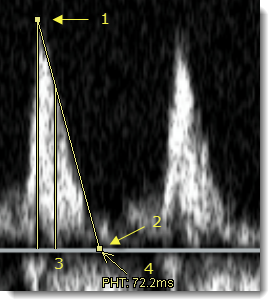

- Κάντε κλικ στο σημείο της μέγιστης ταχύτητας (1) στην περιοχή Doppler της εικόνας υπερηχογραφήματος για να τοποθετήσετε την πρώτη λαβή της σήμανσης.

Η δεύτερη λαβή της σήμανσης εμφανίζεται αυτόματα στη γραμμή βάσης (ταχύτητα = 0 m/s).

- Μετακινήστε τη δεύτερη λαβή (2) κατά μήκος της γραμμής βάσης προς τη σωστή κατεύθυνση και κάντε κλικ για να ολοκληρώσετε τη σήμανση.

Εμφανίζεται μια κάθετη γραμμή (3) στο σημείο όπου η κλίση έχει τη μισή από τη μέγιστη αρχική τιμή της. Το PHT υπολογίζεται και εμφανίζεται σε χιλιοστά του δευτερολέπτου (4).